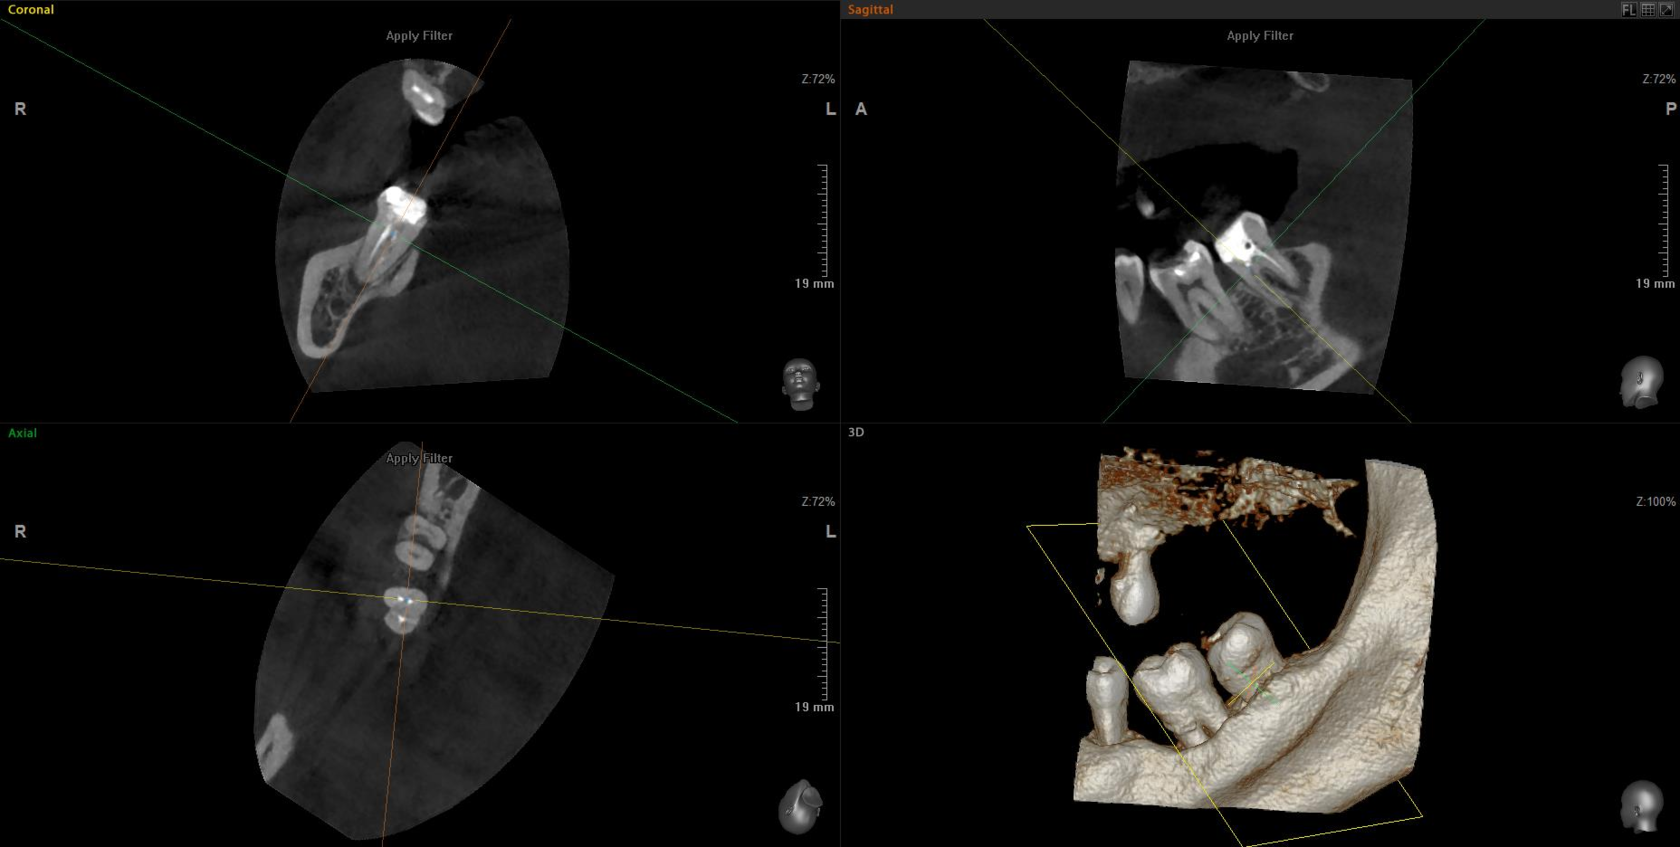

Detailed imaging of a 5×5 cm segment, typically 2-3 teeth